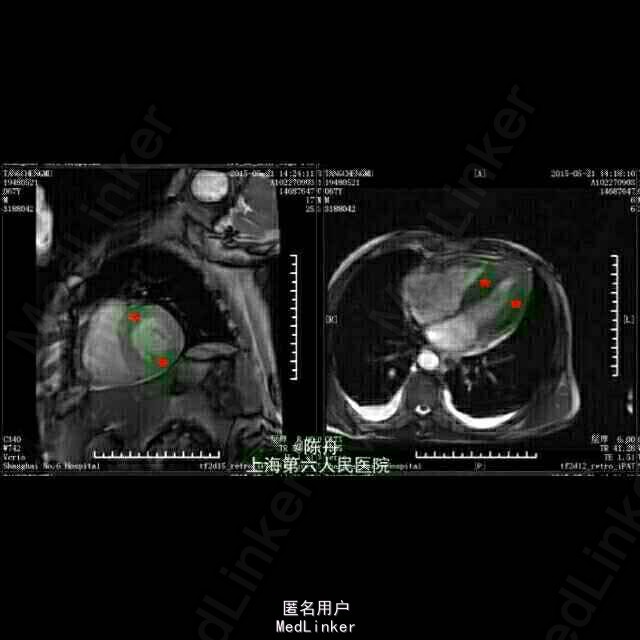

查体:BP 90/60 mmHg,神志清醒,气平,无贫血貌,颈静脉怒张,舌头正常,双肺听诊呼吸音清,双肺未及干啰音。心浊音界大致正常,心率74次/分,律齐,P2=A2,心音减低,各瓣膜区未闻及病理性杂音。腹壁柔软,无腹部压痛,肝脾未触及。双下肢轻度水肿。无关节肌肉疼痛。 辅助检查: 血常规:白细胞 6.7 *10^9/L ,血红蛋白 120 g/L ↓,血小板 218 X10^9/L ,中性细胞百分比 46.5 % 。血沉: 34 mm/h 。C反应蛋白 8.53 mg/L ↑。 肝肾功能:总蛋白 44 g/L ↓,白蛋白 29 g/L ↓,谷丙转氨酶 43 U/L ,谷草转氨酶 72 U/L ↑,总胆红素 9.0 μmol/L ,直接胆红素 5.5 μmol/L ,总胆汁酸 3.1 μmol/L ,前白蛋白 170 mg/L ↓,总胆固醇 2.40 mmol/L ↓,甘油三脂 1.38 mmol/L ,高密度脂蛋白 0.48 mmol/L ↓,低密度脂蛋白 1.48 mmol/L ↓,肌酸激酶 194 U/L ↑,CK-MB 16.0 U/L ,乳酸脱氢酶 334 U/L ↑,α羟丁酸脱氢酶 282 U/L ↑,血清钾(干式) 3.3 mmol/L ↓,血清钠(干式) 134 mmol/L ↓,血清氯(干式) 91 mmol/L ↓,钙(干式) 1.94 mmol/L ↓,尿素(干式) 19.0 mmol/L ↑,肌酐(干式) 87 μmol/L。 血气:PH 7.40 ,二氧化碳分压 39.7 mmHg ,氧分压 79.8 mmHg 生化报告:清蛋白 49.2 % ↓,α1球蛋白 8.6 % ↑,α2球蛋白 18.6 % ↑,β1球蛋白 6.3 % ,β2球蛋白 2.9 % ↓,γ球蛋白 14.4 % 。 免疫:血清KAPPA轻链 2.80 g/L ,血清LAMBDA轻链 0.26 g/L ↓,κ/λ比值 10.81 ↑。 免疫:尿KAPPA轻链 1260.00 mg/L ↑,尿LAMBDA轻链 4.62 mg/L ↑。 其它免疫指标全阴性. 甲状腺功能:游离T3 2.81 pmol/L ↓,游离T4 19.94 pmol/L ,促甲状腺激素 2.71 mIU/l 。 生化:肌钙蛋白-I 0.305 ↑,CKMB 9.6 ug/L ↑,B型钠尿肽(BNP) 1260.00 ng/L ↑。B型钠尿肽前体(proBNP) >35000 ng/L ↑。 心脏超声: 1.左心房稍扩大2.左室壁增厚3.未见节段性室壁运动异常。EF:60% 24H动态心电图:1.窦性心律2.房性早搏(时呈成对,代偿后见室性逸搏)3.房性心动过速(短阵)。终止后呈窦性,交界性逸搏,恢复时间<2秒。4.室性早搏(多源性,时呈成对,二联律)5.ST段下移,T波倒置(持续性:第一,三通道导联,呈水平型)6.未见传导异常。 心脏 MRI:1.双心室壁增厚,收缩功能保留,心肌淀粉样变可能。2.微量心包积液,少量双侧胸腔积液。 胸部CT:1.慢性支气管炎,两肺多发微小结节,考虑炎性肉芽肿可能。2.心脏增大,两侧胸腔积液,伴下肺膨胀不全。 电子胃镜:糜烂性浅表性胃炎。病理:阴性。

讨论:患者为67岁男性,长期务农,发病以右心功能不全为主要表现:颈静脉怒张,胃肠淤血,双下肢水肿,实验室检查:肌钙蛋白-I 0.305 ↑,CKMB 9.6 ug/L ↑,B型钠尿肽(BNP) 1260.00 ng/L↑ ,B型钠尿肽前体(proBNP) >35000 ng/L ↑,κ/λ比值升高,尿中有大量KAPPA轻链,肝肾功能及其它免疫指标大致正常;心脏超声示左心房稍扩大,左室壁增厚,EF:60%。心脏MRI示双心室壁增厚,收缩功能保留,心室肌细胞间可见颗粒样物质沉积。结合患者临床表现及实验室检查,及肾内科、内分泌、血液科会诊意见,考虑心脏淀粉样变。遗憾的是迄今无有效药物治疗此疾病。 【声明:内部资料,仅供学习参考,请勿转载或发表至专业杂志,@陈舟医生】